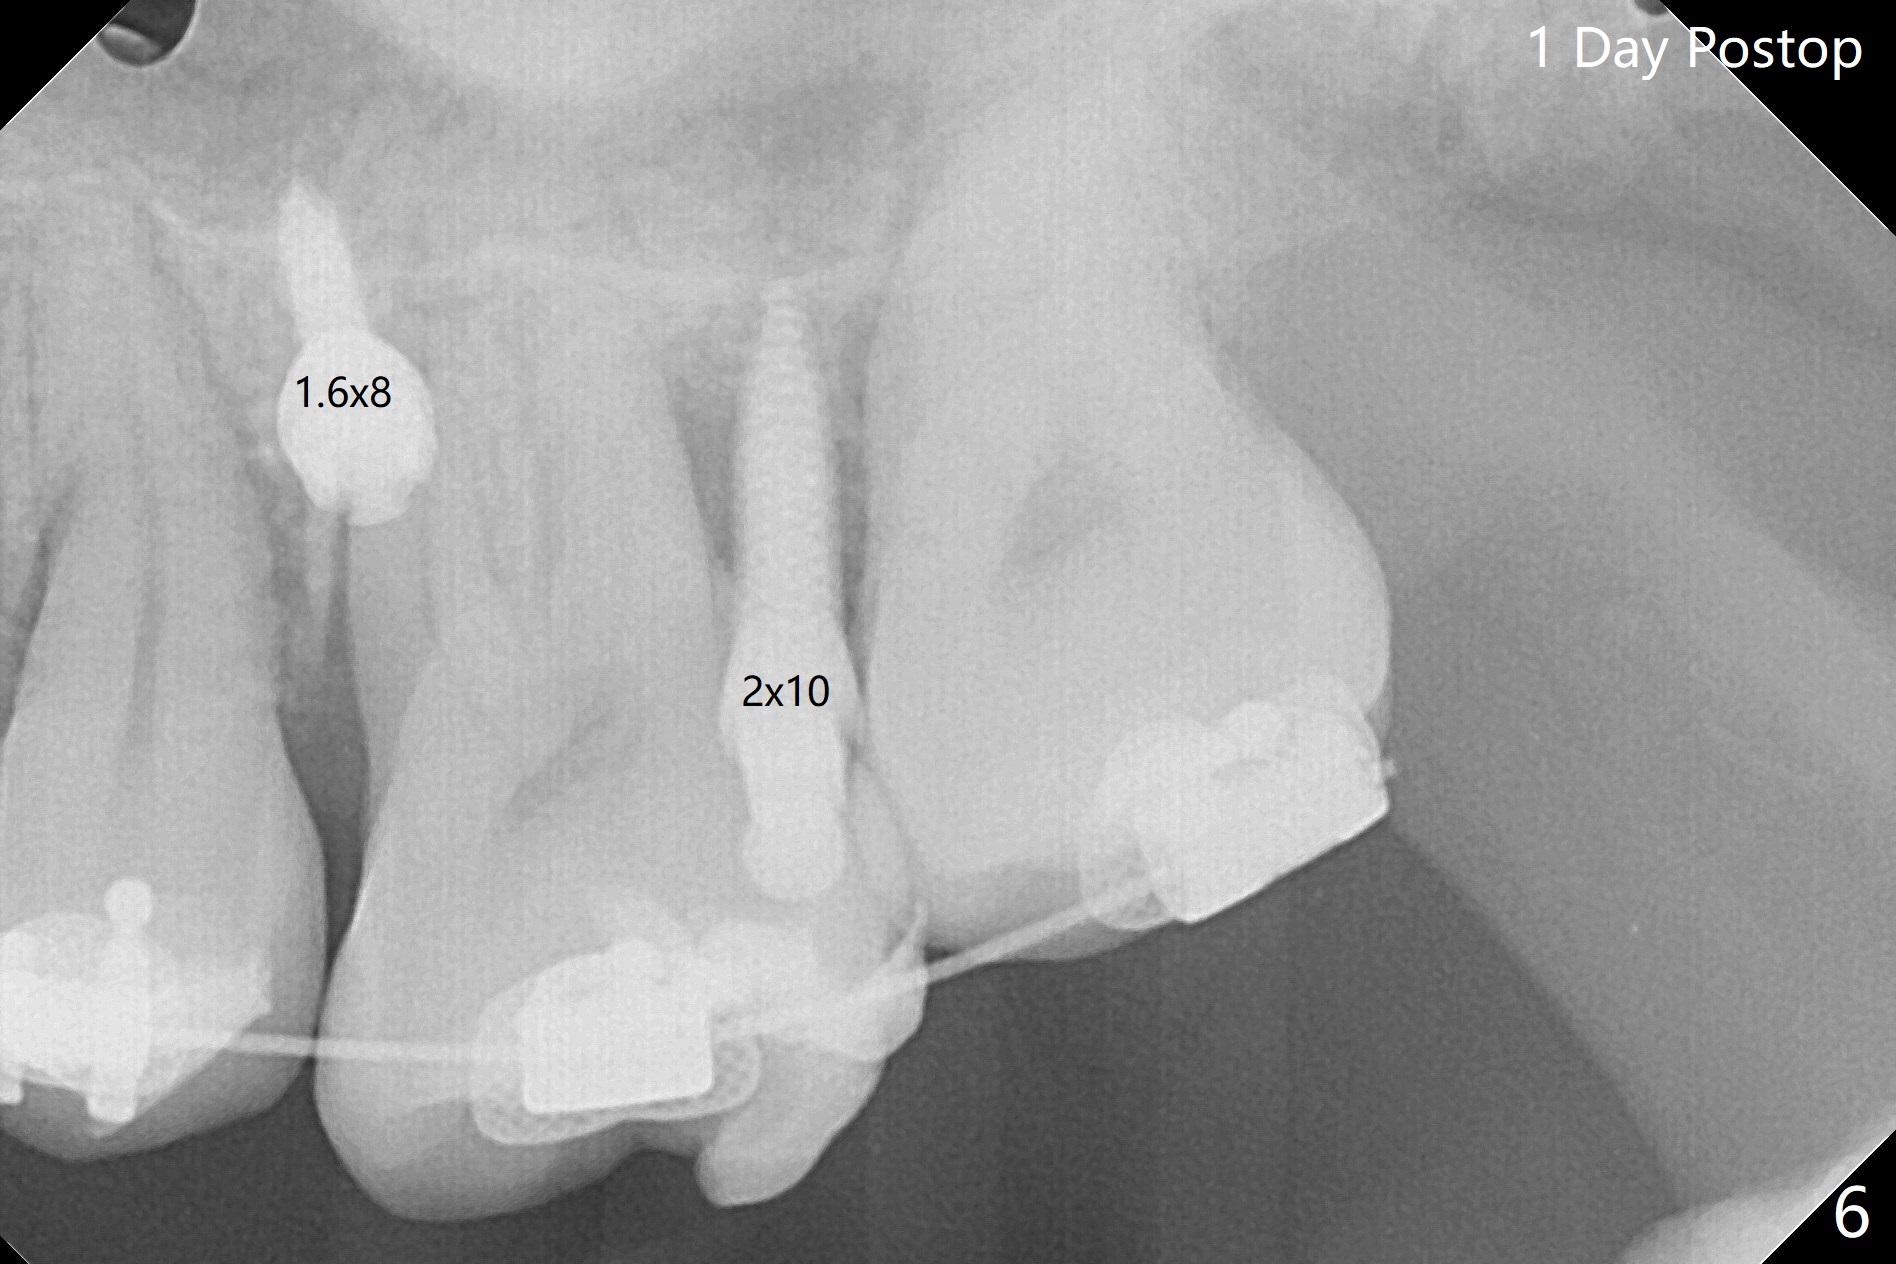

矫正器放置后一个月,正好有充裕时间,匆忙研究全景片(最好CT),好像左上6近中间隙大,近中颊侧,远中腭侧似乎是种植位点(图一:白圆圈),植入越高越宽,不容易伤及邻牙牙根。但是微型植体种植原则是必须种植在角化龈,减少炎症(以前不明白为什么)。当植体在移动牙龈植入时(图二:白箭头),牙龈浮起来,估计非角化牙龈也不能与植体产生紧密结合。取出后,完全可以在6近中颊侧角化龈植入,但是仔细检查发现远中颊侧角化龈更宽,所以在那里扎根(图二:黑箭头),因此腭侧就得选择近中(图三)。微型植体可以即刻使用,power chains常滑脱,压迫牙龈,在这个病例很可能进入远中牙间隙,所以需要在远中边缘嵴加树脂(图四,五:* (1.6x8mm))。第二天远中颊侧植体松动,取出后,插入2x10毫米一段式植体,仍然松动(图六)。CT显示植体下缘穿破牙槽骨(图七,骨质吸收严重与图八近中牙槽骨高度对比)。如果在近中颊侧重新植入微型植体,必须使用6毫米长植体(图九),所以最好在远中颊侧重新植入(图十:红色),缺损区(黑色)植骨。在使用14 niti时,左下7松动,病人同意拔除8,以后后推7,然后6种植(图十一:(左上8已拔除(x))),同时左上6远中植骨,左下8远中牙槽窝放置浸泡PRF液体胶原塞(图十二:1),近中牙槽窝粘性骨粉(2),最后牙槽窝上部PRF膜(3),PGA缝线。可能需要Cytoplast。